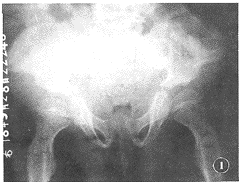

1.1 例1:男,12岁。患儿出生时发育正常,于1岁左右时开始出现体格、智力发育迟缓且逐渐加重伴进行性痴呆。体检:身材矮小,四肢短小畸形,身高96 cm。头大,痴呆,面容丑陋,角膜混浊,额部和两颊突出,塌鼻,牙齿残缺不齐。心肺正常。腹部膨隆,肝脾肿大且质硬。四肢关节僵硬,髋、膝关节外翻。双手指短而弯曲成爪状。腰背部无后突畸形。实验室检查:尿中硫酸软骨素B和硫酸肝素显著增加。甲苯胺蓝染色(Toluidine Blue),骨髓及血淋巴细胞、粒细胞中均见呈浅紫色、大小不等、形状不同、成丛存在的异染性粘多糖颗粒(即Reilly小体)。X线表现:颅骨前后径增长呈舟状,蝶鞍前床突下塌,蝶鞍变浅平拉长呈鱼钩状。T12和L3椎体较小,椎体前下缘呈鸟嘴状突起,无后突畸形。骨盆两髂骨翼外翻,基底部变尖,髋臼浅平且不规则,两髋外翻(图1)。四肢骨骨干粗短,骨骺发育明显延迟且未融合,双侧尺挠骨远端关节面倾斜分离,2~5掌骨粗短,近端变尖细,腕骨小而不规则。

图1 骨盆正位片:两髂骨翼外翻伸展,基底部变尖,髋臼浅而不规则,髋外翻,坐骨大切迹深凹

1.2 例2:(例1之妹),女,9岁。其发病过程、临床和X线表现与例1基本相同,唯其尺挠骨、手腕诸骨的表现较为典型(图2)。